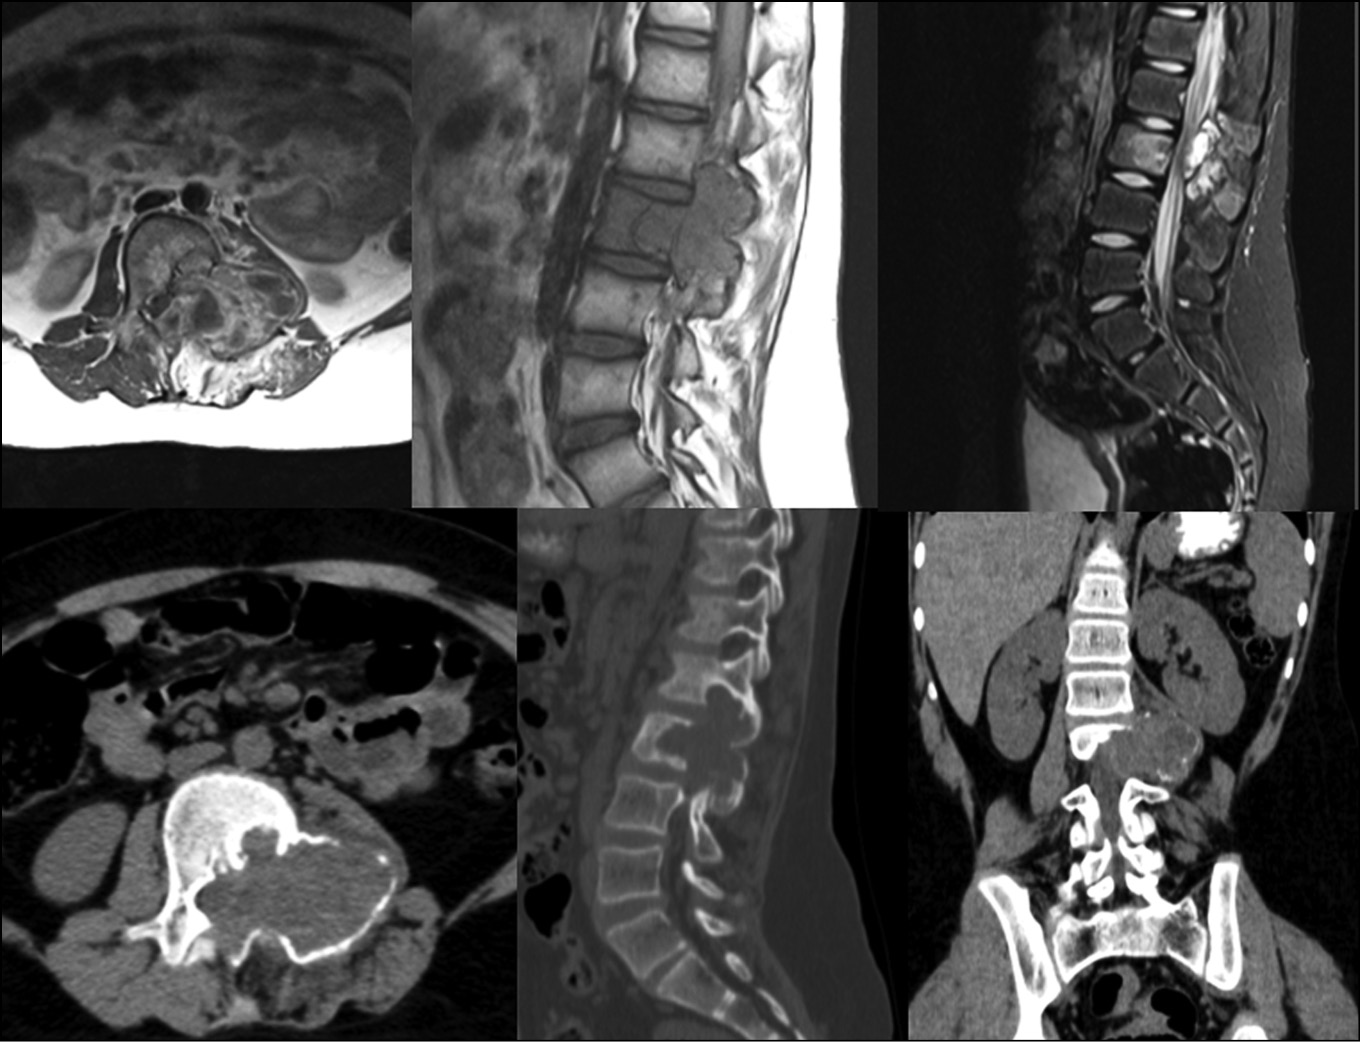

Клинический пример — пациентка 15 лет.

Обратилась по месту жительства с болями в поясничном отделе позвоночника. При попытке консервативного лечения, боли резко усилились. При дообследовании по данным КТ и МРТ поясничного отдела позвоночника выявлено патологическое образование в L3 позвонке с формированием стеноза позвоночного канала (рис. 3).

Рис. 3. КТ и МРТ исследования при поступлении

Fig. 3. CT and MRI examinations upon admission

При проведении Лечебно-диагностической пункции получено высокое давление (242 мм водного столба). Отправленный на гистологическое исследование материал подтвердил диагноз аневризмальная киста позвонка L3. Проводились повторные пункции с интервалом в 1.5 месяца. После 3 манипуляции отмечено стойкое снижение болевого синдрома, снижение степени активности кисты и стеноза позвоночного канала.

По данным КТ исследований отмечены признаки частично репарации костной ткани позвонка (рис. 4). Далее было проведено открытое хирургическое вмешательство (рис. 5) в объёме — ТПФ на уровнях L2-4 позвонков, гемиламинэктомия L3 справа, удаление оболочек анверизмальной кисты, декомпрессия позвоночного канала., комбинированная пластика костного дефекта с применением ауто- и аллотрансплантатов. Время хирургического вмешательства составило 2 ч. 15 мин. Объём кровопотери — 240 мл.

Рис. 4. КТ и МРТ через 5 месяцев на фоне проведенного пункционного лечения с менее выраженным стенозом содержимого позвоночного канала

Fig. 4. CT and MRI results after 5 months of puncture treatment with less pronounced stenosis of the spinal canal